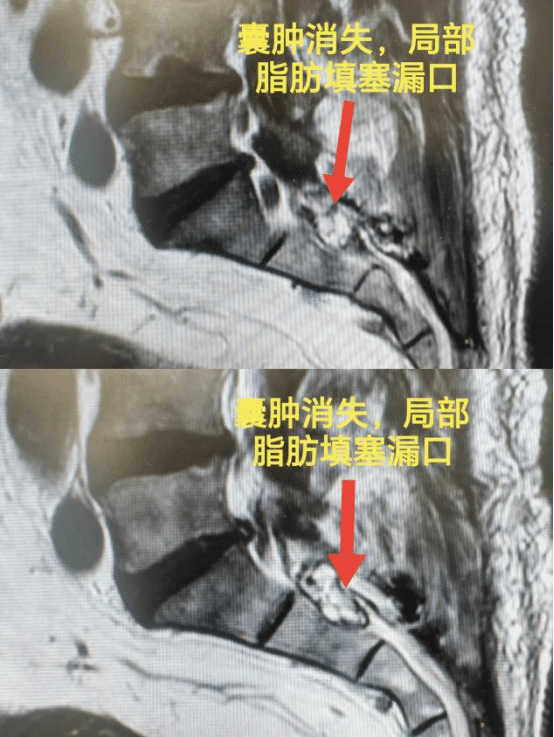

术前

术后

团队与张大爷及其家属进行了详细的沟通,决定行骶管囊肿切除术。手术在麻醉科的配合下顺利完成,术中切除囊壁、填塞封合瘘口,患者术后2天即可下地行走,症状好转。